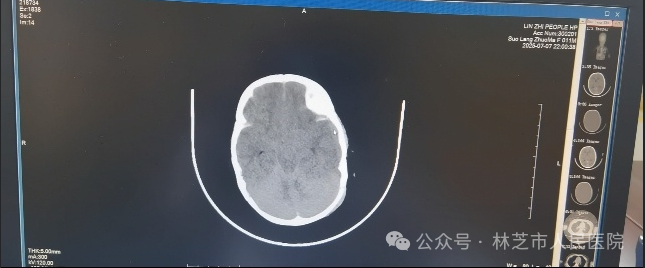

7月7日晚9时,还处于高原适应期的张春敏主任接到儿科值班医生的紧急电话:一名昏迷不醒、呼吸微弱的幼儿被送入医院,双侧瞳孔不等大,生命危在旦夕。尚未克服高原反应的张春敏主任立即电话中指导抢救,顶着高原缺氧的状态急速奔赴医院。查体发现患儿左侧枕部淤肿,凭借丰富经验,他迅速判断患儿存在严重颅脑创伤、颅内出血合并脑疝,当即汇报医院医务科启动绿色通道,连夜联系影像科,并同值班医生护送患儿完成急诊头颅CT检查,确诊为“左侧额颞顶叶脑挫伤、蛛网膜下腔出血、硬膜下/外出血、脑疝”。时间就是生命,张主任立即联系了同批援藏专家神经外科谢韬主任到场评估手术救治。

7月7日晚急诊头颅CT情况